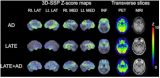

中国原创头戴随动式脑PET问世,打破传统固定扫描局限

深圳湾实验室生物医学工程研究所彭旗宇团队于2026年4月30日在国际核医学顶级期刊《Journal of Nuclear Medicine》(JNM)在线发表研究成果,发布了自主研发的新型头戴随动式脑PET系统。该系统突破了传统脑PET要求受试者必须保持固定卧位的限制,通过让成像设备围绕头部随动,实现了在清醒、自然及动态状态下进行脑功能成像的可能。研究团队依据NEMA NU 2-2018标准对该系统进行了系统评价。数据显示,其空间分辨率达2.29毫米,灵敏度720.2 cps/M... 2026-05-06 核医学PET/CT